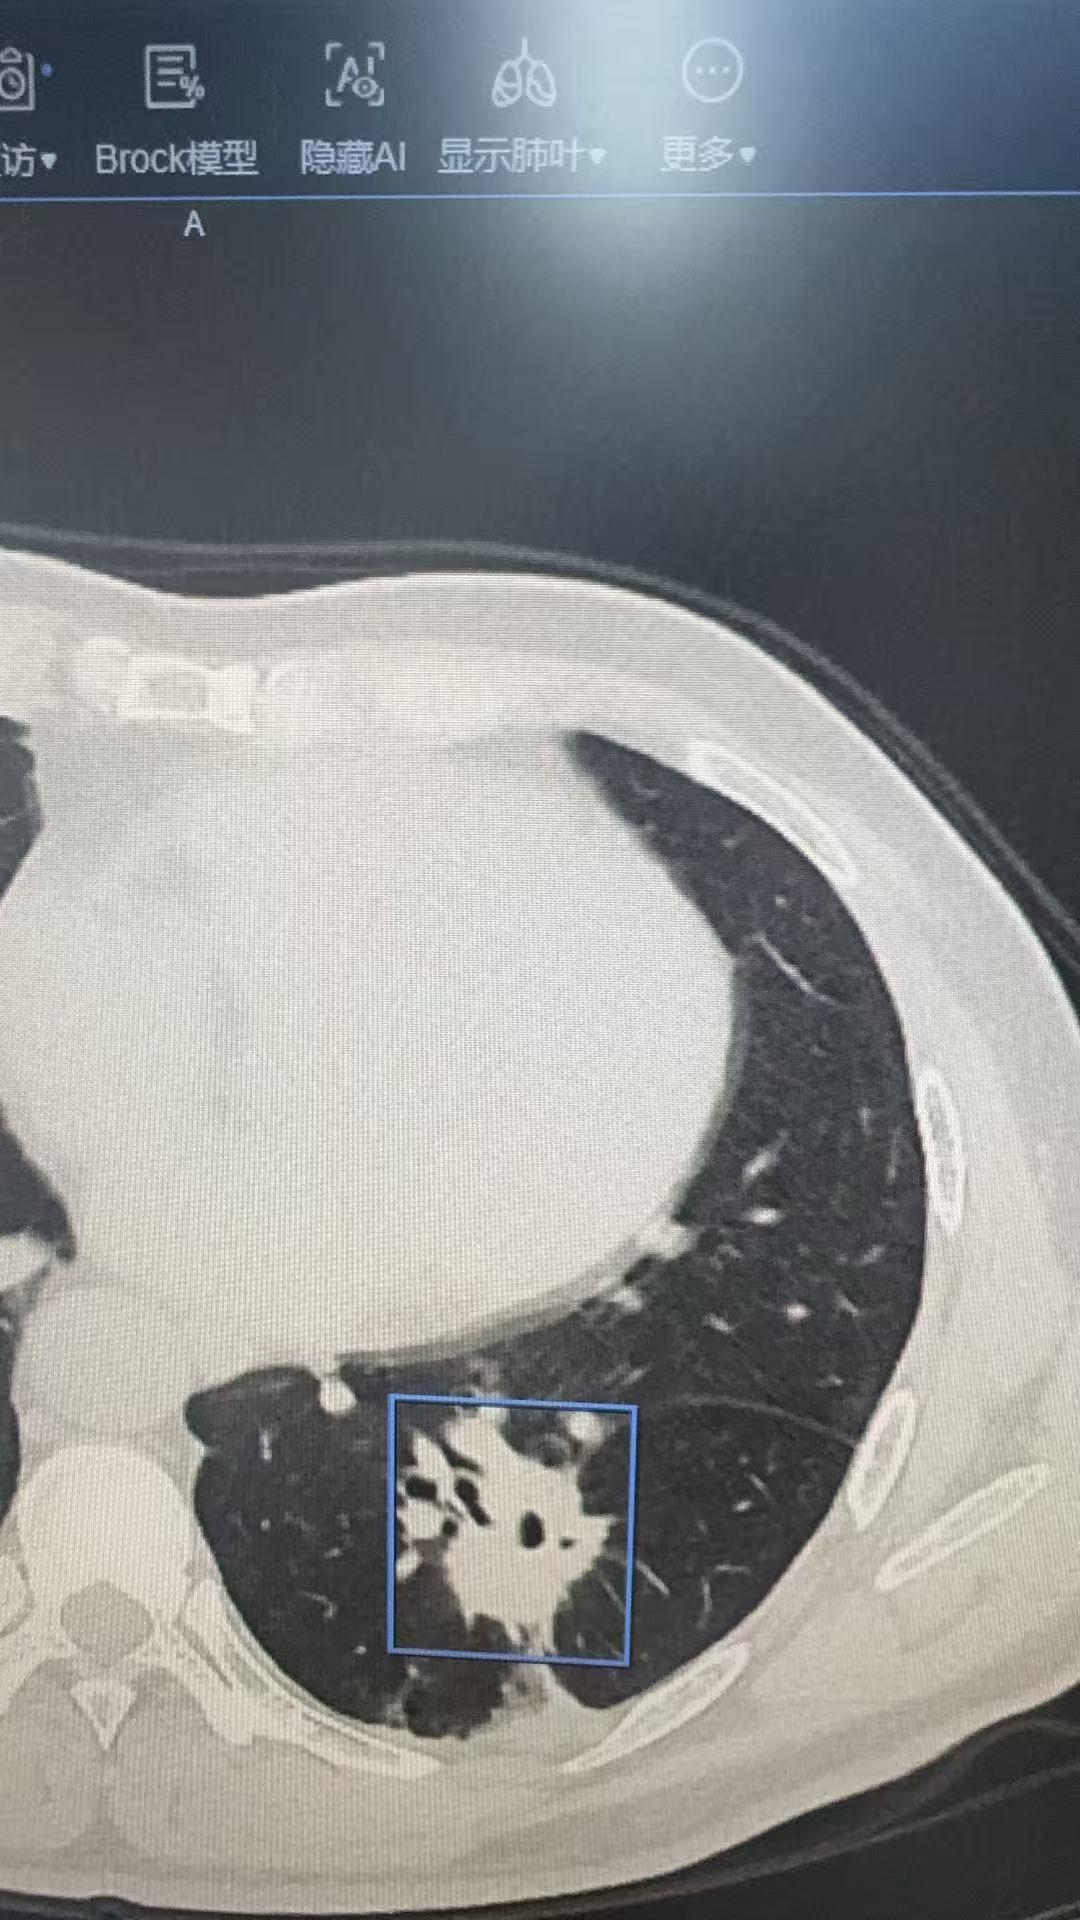

左下肺实性肺癌。左下肺实性肺癌,清扫了第4-14组淋巴结……对于实性的...

图识肺结节……图识肺结节……可以如图发在评论区,我会抽空回复……

左侧同时切三个高危结节。左侧同时切三个高危结节,避免未来再做同侧手术……

这个8mm的微浸润腺癌,看了很多地方没看出来,我们团队没有漏掉这个恶性...